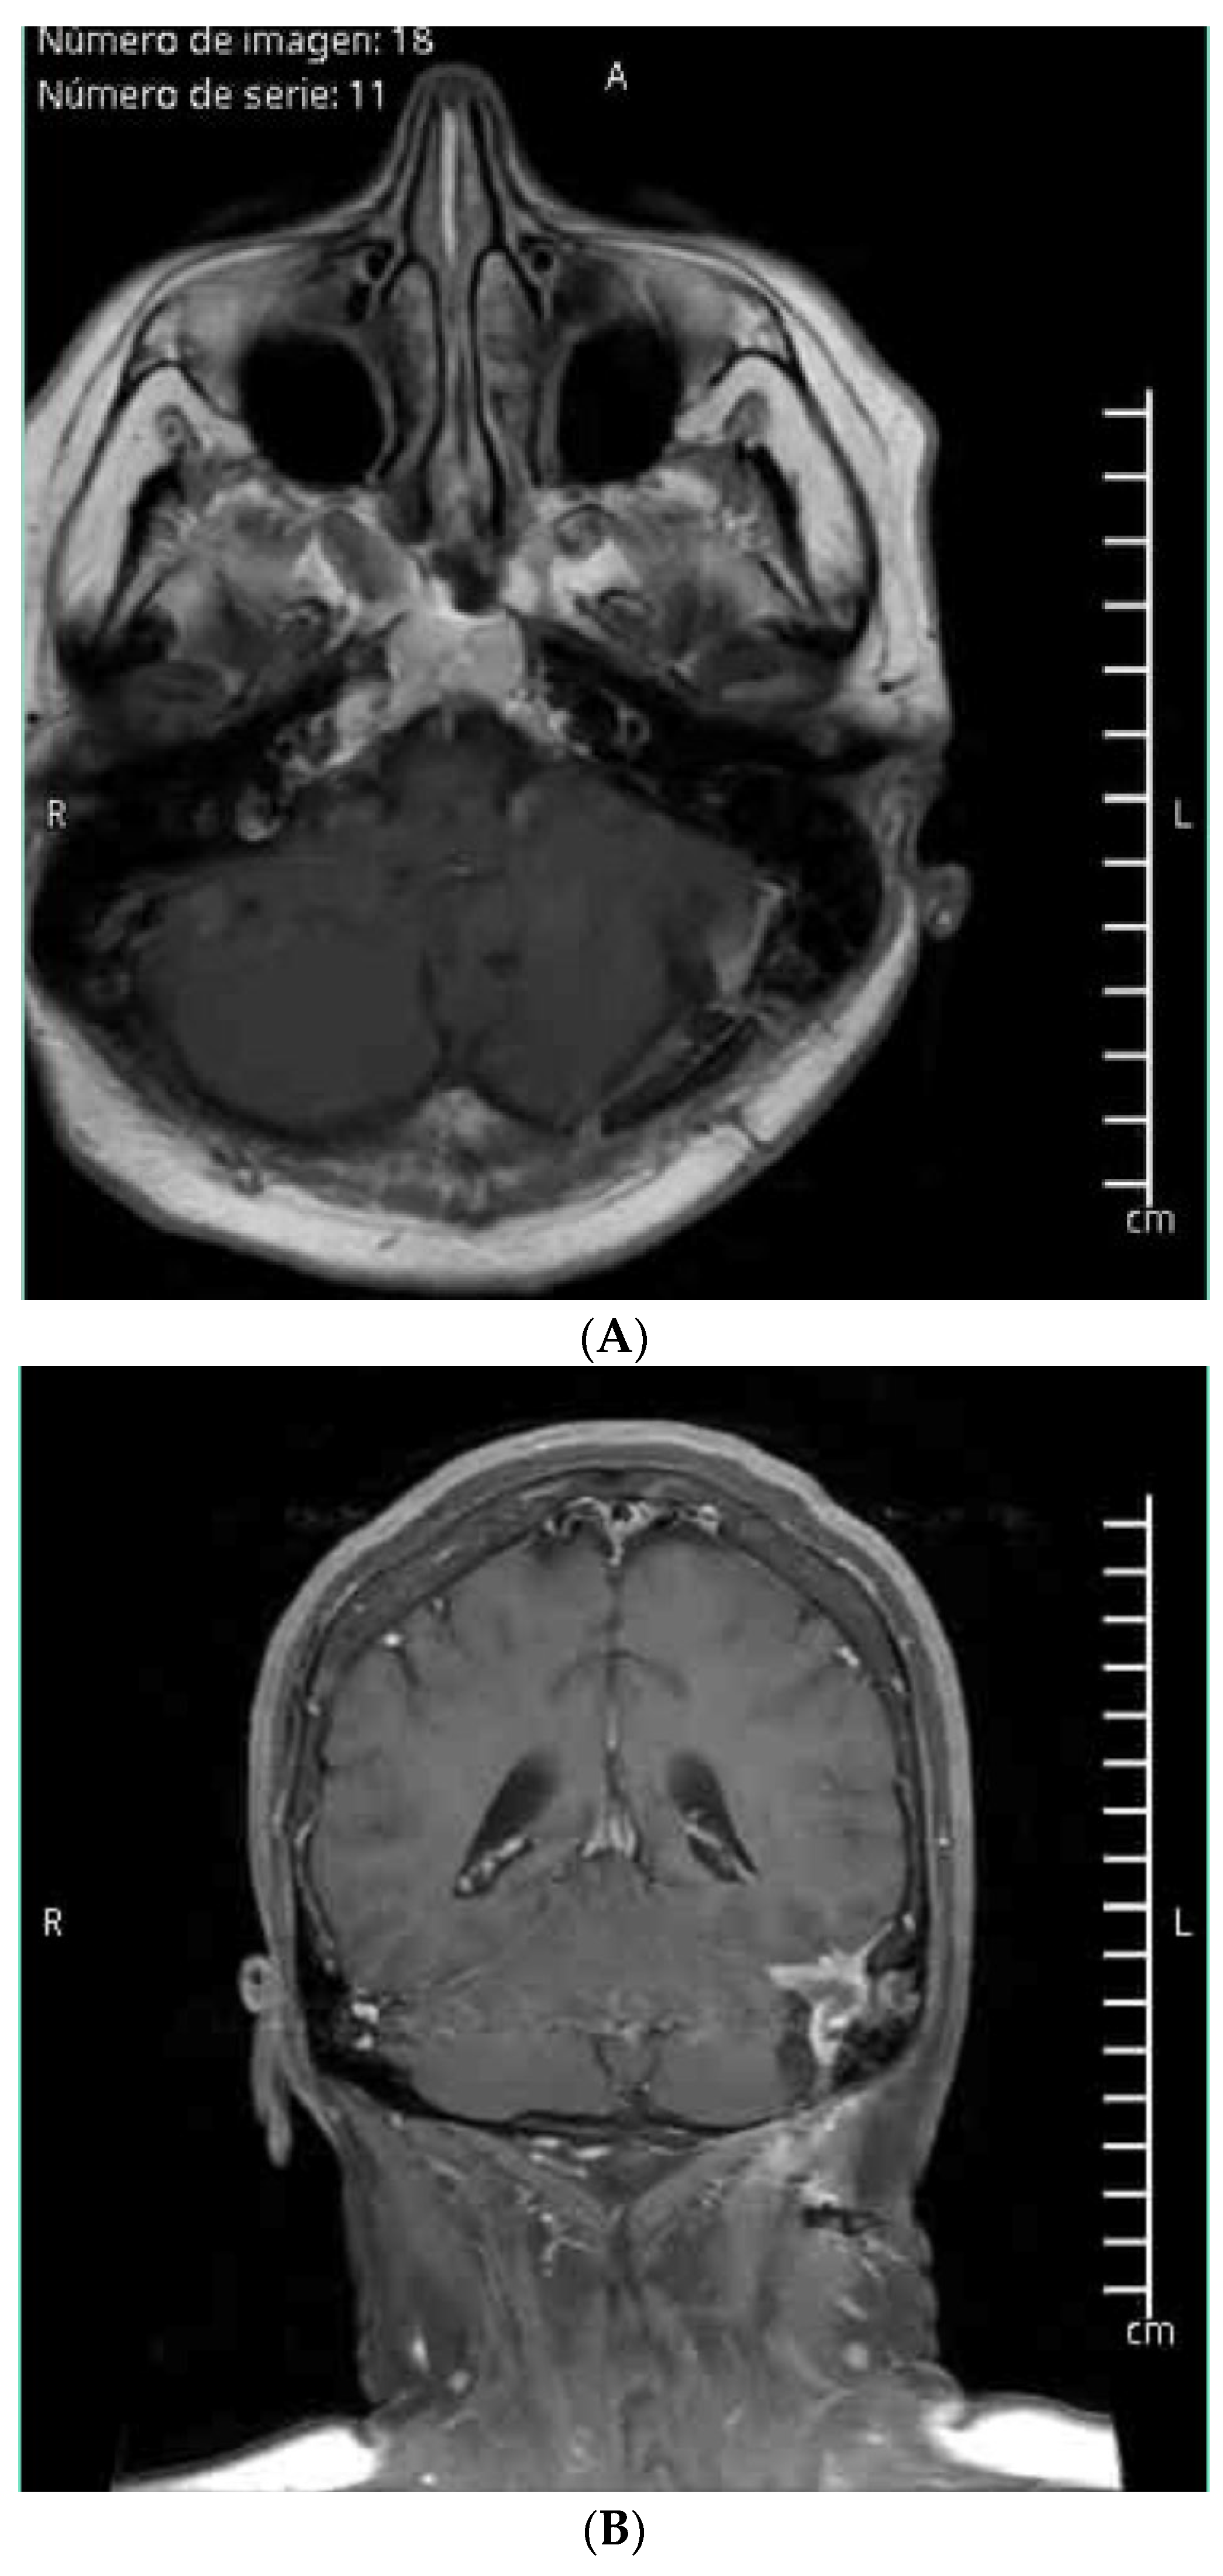

- Case 1: The AR-assisted retrosigmoid approach facilitated an 80% subtotal resection of a complex infratentorial meningioma, resulting in significant symptomatic relief and minimal postoperative complications. This underscores the potential of AR to enhance surgical outcomes in challenging anatomical regions (on the sigmoid and transverse sinuses). (Figure 1 and Figure 2). The patient’s rapid recovery and favorable outcome further emphasize the clinical advantages of AR-guided surgery.